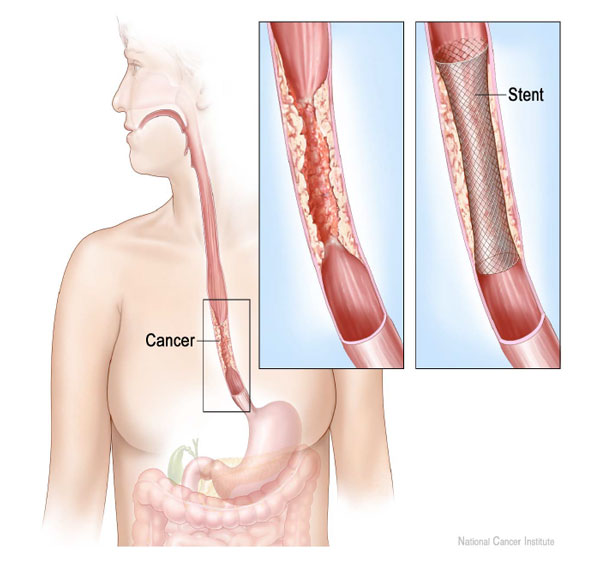

Esophageal Stent TrialQuest Inc

Esophageal Stenting Video Medical Video Library

Esophageal Stenting Video Medical Video Library